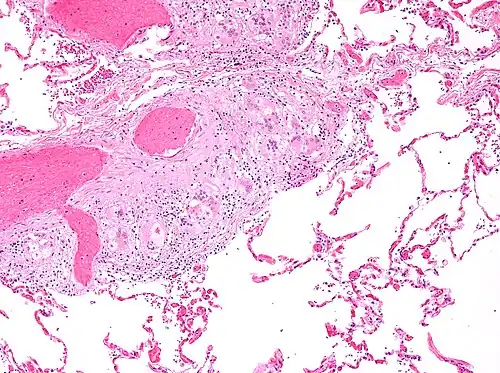

Micrograph of asteroid bodies in pulmonary sarcoidosis. H&E stain. -